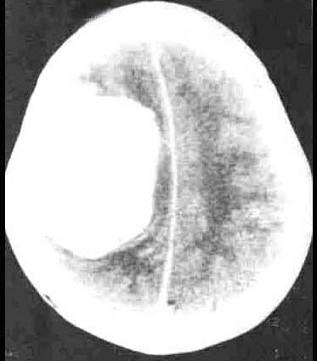

问题 脑膜瘤(如图所示)最常见的部位是()

选项 A.大脑镰 B.蝶骨嵴 C.大脑凸面 D.鞍结节 E.矢状窦旁

答案 E